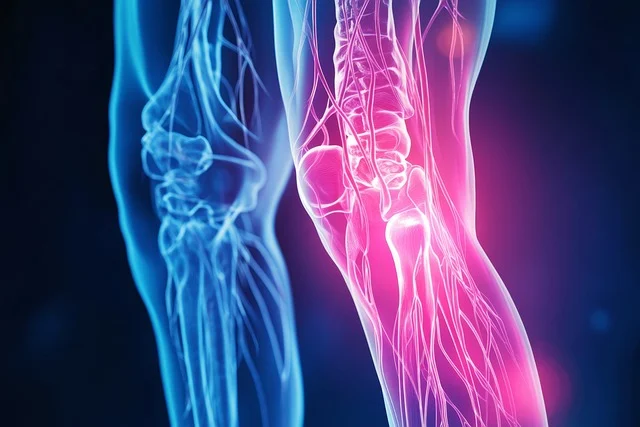

인공관절은 무릎에 통증과 뼈와 뼈가 맞닿아 무릎통증과 마모절감 수술에 제공되는 의료기기입

니다. 무릎통증이 너무 심해 걷지 못하게 되어 인공관절 수술을 하게 되는 것입니다. 매우 심각한 무

릎통증과 걷지도 못하게 되는 퇴행성 관절염 4기가 되기 전 진단을 받고 치료하는데 관심을 가져야

한다.

- 인공관절은 연골이 마모가 되어 뼈와 뼈가 부딪치면서 고통을 겪으며 걷지를 못하게 되는 퇴행

성 관절염 수술에 공급되는 의료수술 기기입니다.